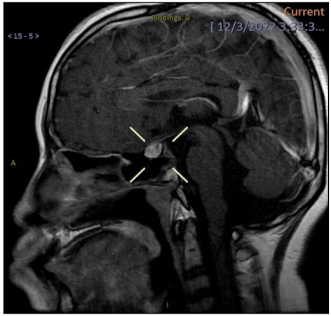

Results: A total of 8 cases were retrieved with a mean age of 5.7 years (range 2–8 years). Detailed individual and family history was taken from all patients and complete clinical examination was performed. Vaginal swabs were taken, bone age was assessed and a pelvic ultrasound of internal genitalia was performed. In 2 cases pelvic and brain MRI were carried out to assist differential diagnosis. Hormone testing and especially LH-RH (Luteinizing Hormone Releasing Hormone) stimulation test were prescribed when necessary. Moreover, n 3 cases (37.5%) vaginoscopy was deemed necessary. Conclusively, 3 cases (37.5%) were diagnosed with precocious puberty, 1 case (12.5%) was diagnosed with genital hemangioma, 2 cases (25%) were diagnosed with vaginal foreign body, and in the 2 remaining cases (25%) no diagnosis was reached and thus were assigned to a monitoring schedule.